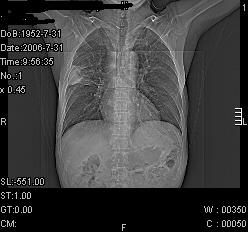

患者,男,54岁,咳嗦,咳痰20天。抗炎治疗2周。现esr76mm/h,目前患者症状明显好转,但发现两次ct片未见明显变化。两次分别做与7.25、7.31。第一次诊断右肺上叶炎症累计胸膜。大家看,从影像上内排除结核吗?

结核的可能性非常大,右上肺病变应该考虑干酪性肺炎。理由:

1.纵隔内多发淋巴结肿大。

2.esr76mm/h。

3.虽经抗炎治疗肺窗病灶有所吸收、减小,但纵隔窗病灶形态、密度、范围无明显变化。如果是单纯的大叶性肺炎,“抗炎治疗2周,目前患者症状明显好转”病灶应该基本消散了,至少也处于吸收消散期,密度变淡、范围变小。同时本病例所示其内的密度不均匀,见多发大小不一空洞样影也不符合大叶性肺炎吸收消散期表现。

病灶特点:片状 索条 结节混杂影,部分融合,密度不均,广泛累及相应胸膜.

临床治疗;二周未吸收.但症状好转.

多考虑:肺结核.